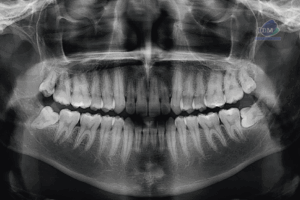

Paciente masculino de 20 años de edad, es referido al Instituto de Diagnóstico Maxilofacial – IDM por dolor en zona mandibular.En la radiografía panorámica (Figura